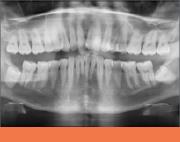

Rare Presentations of Sialolith and Tonsillolith with Ghost Images

Distinguishing true panoramic images from ghost images is a crucial skill that may help avoid unnecessary surgical intervention. This article describes cases of a giant sialolith and tonsillolith, each of which appeared bilaterally due to ghost images, and discusses their clinical and radiographic characteristics.Read the case studies today.